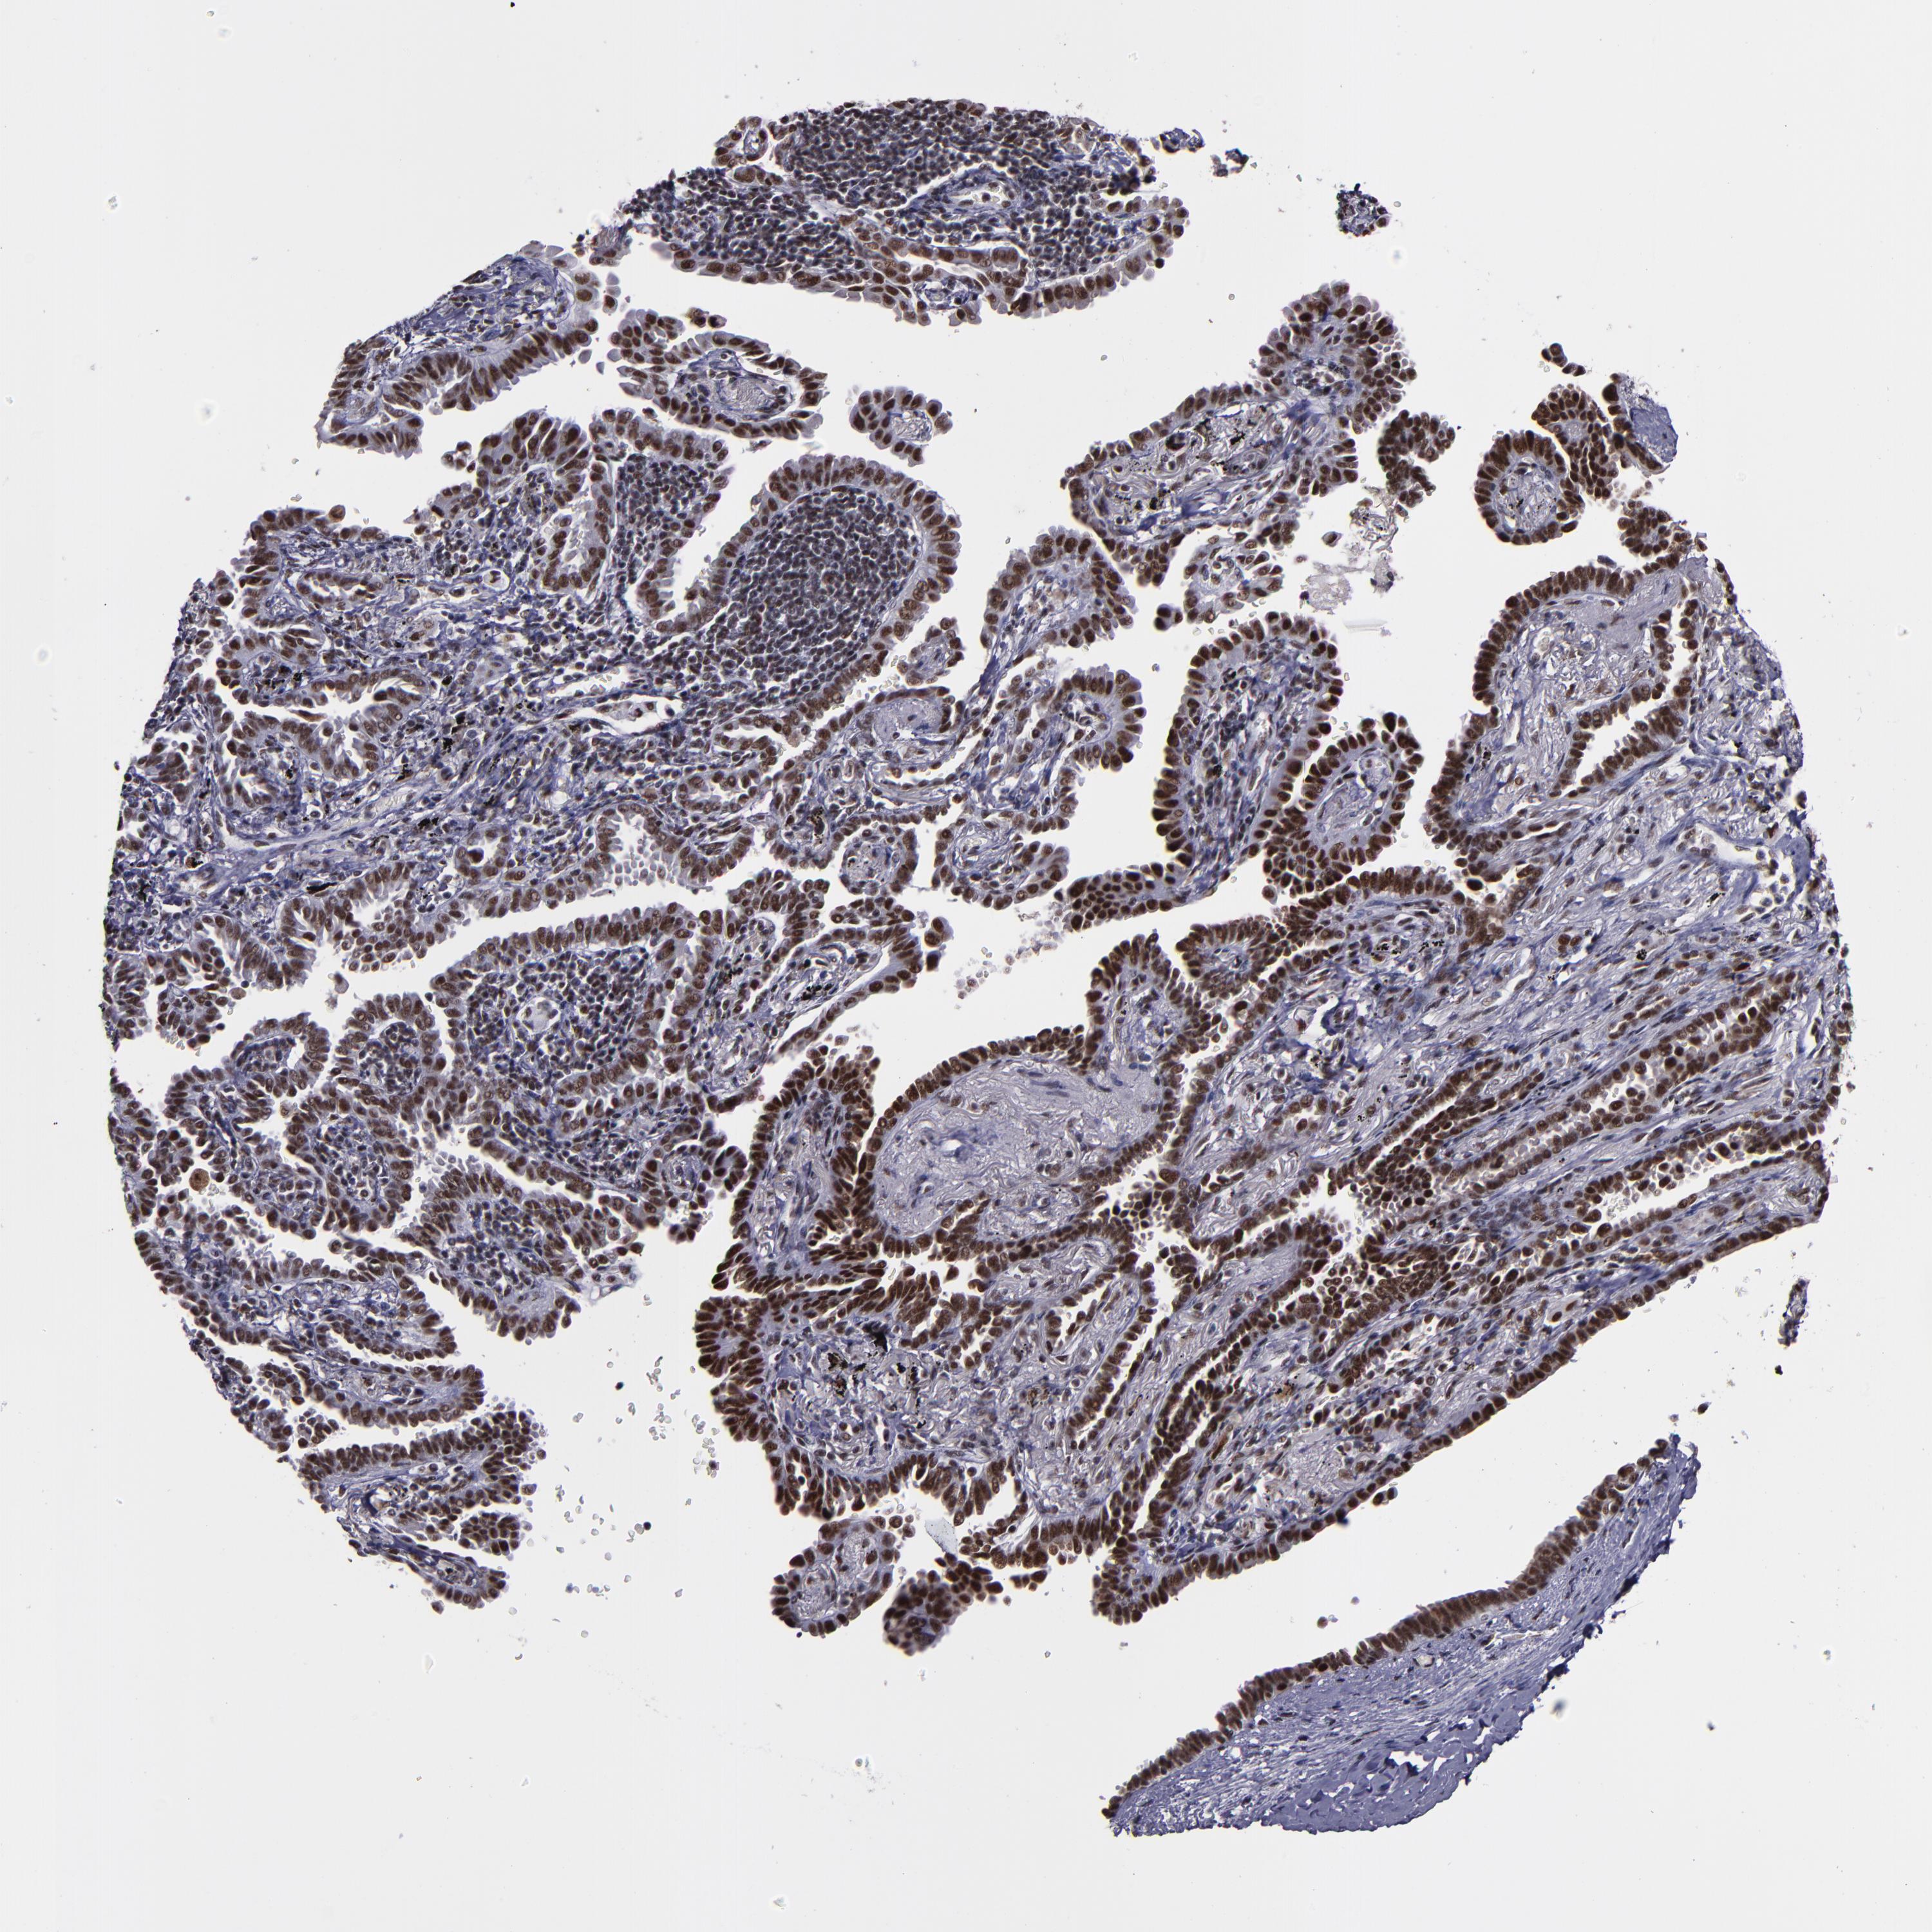

CANCER LUNG CANCER Show tissue menu

LUAD TCGA LUAD VALIDATION LUSC TCGA LUSC VALIDATION PROTEIN LUAD CPTAC PROTEIN LUSC CPTAC PROTEIN EXPRESSION

ANTIBODIES

AND

VALIDATION